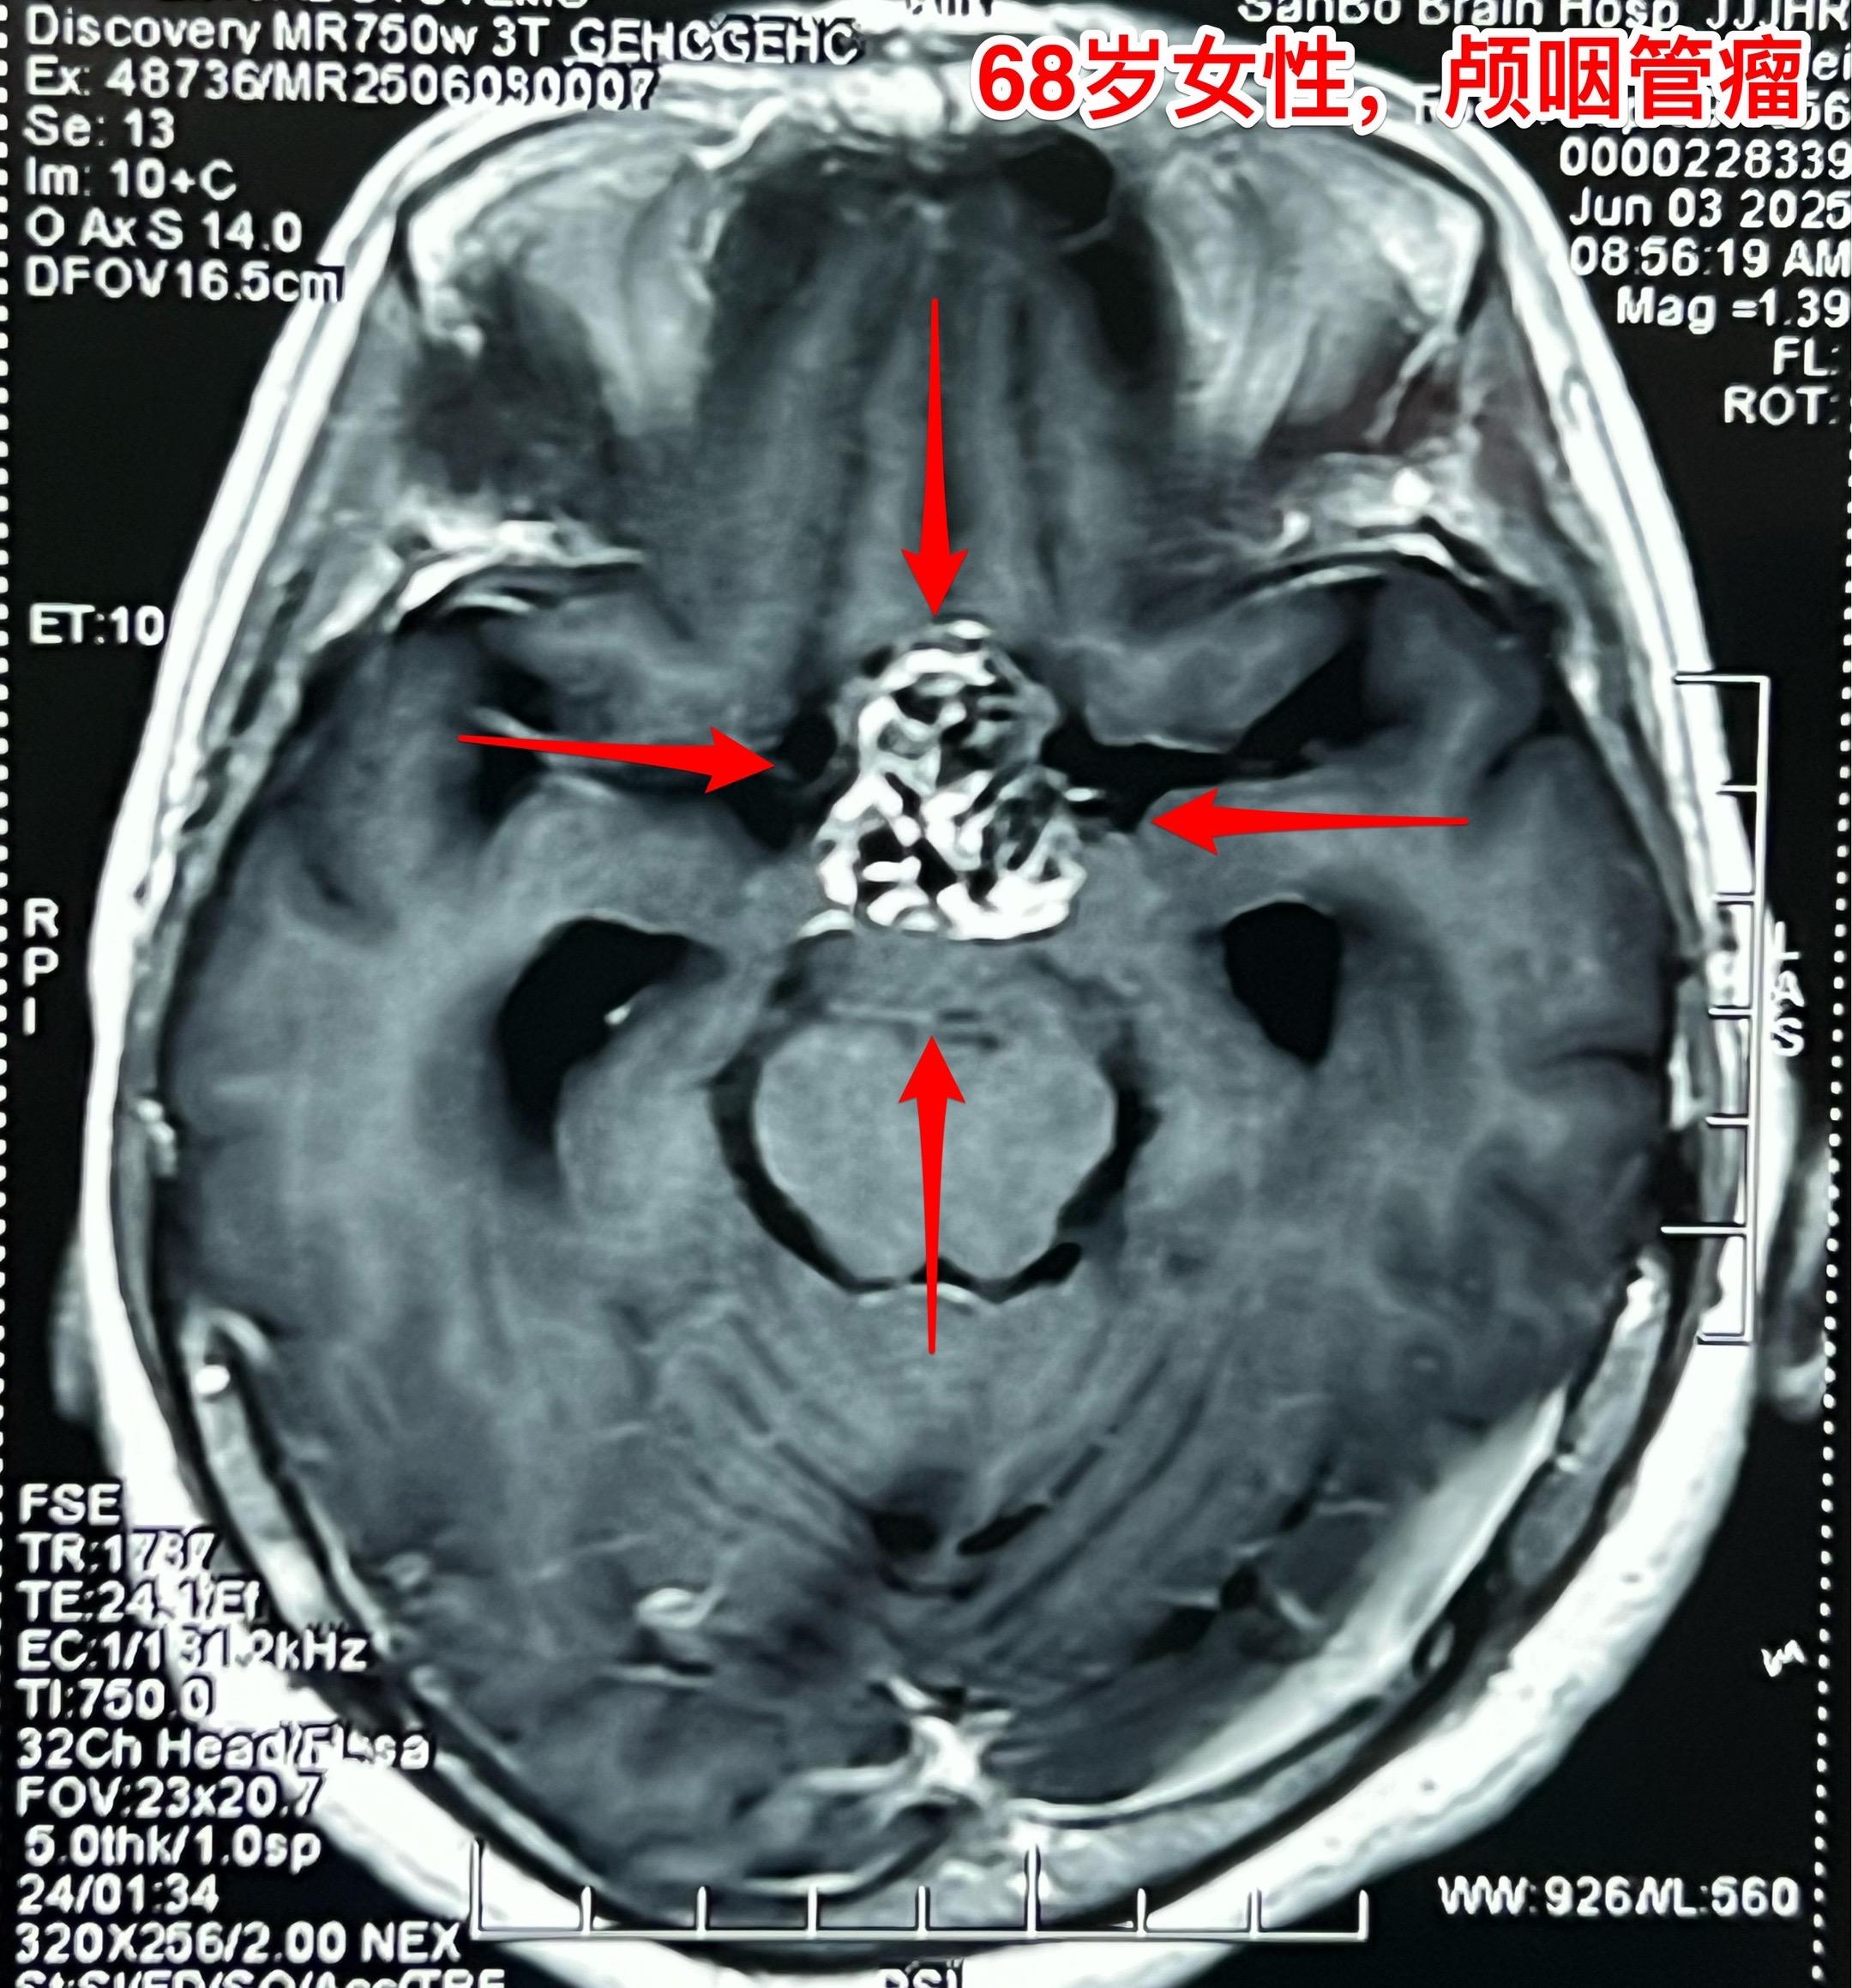

68岁老人患颅咽管瘤是否可以作手术? 颅咽管瘤并非小孩子的病,老年人也可以患颅咽管瘤。 过去十年间我科治疗过颅咽管瘤患者共计1153例次,其中53例患者年龄在60-74岁。 所以,老年人患颅咽管瘤也不是手术禁忌。 这个68岁南通市女病人因颅咽管瘤造成视力下降、头晕症状,住院前一天出现反复呕吐症状,提示颅内压升高,所以应该尽早作手术,否则会造成生命危险。2025年6月8日作了开颅手术,颅咽管瘤得到完全切除。幸运的是垂体柄受肿瘤侵蚀的不严重,得以保留。今天是手术后第